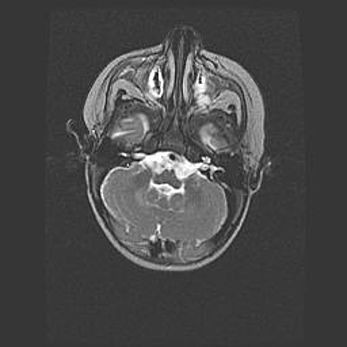

Множественные кисты обоих полушарий головного мозга, наибольшая из них в правой затылочной области. Ассиметричная атрофическая гидроцефалия.

Возраст: 7 месяцев

Вес: 5660 г

Пол: мужской

Окружность головы: 41,5 см

Срок гестации: 28-29 недель

Кисты головного мозга развиваются в результате многоочаговых некрозов вещества мозга и возникают вследствие перенесенной перинатальной инфекции, менингитов, энцефалитов, асфиксии, родовой травмы, расстройств мозгового кровообращения различного генеза. Образованию кист в веществе головного мозга плодов и новорожденных способствуют такие факторы, как высокое содержание в нем воды, недостаточная (или отсутствие) миелинизация и слабая астроглиальная реакция на повреждение.

Кисты могут сочетаться с гидроцефалией и другими поражениями головного мозга.